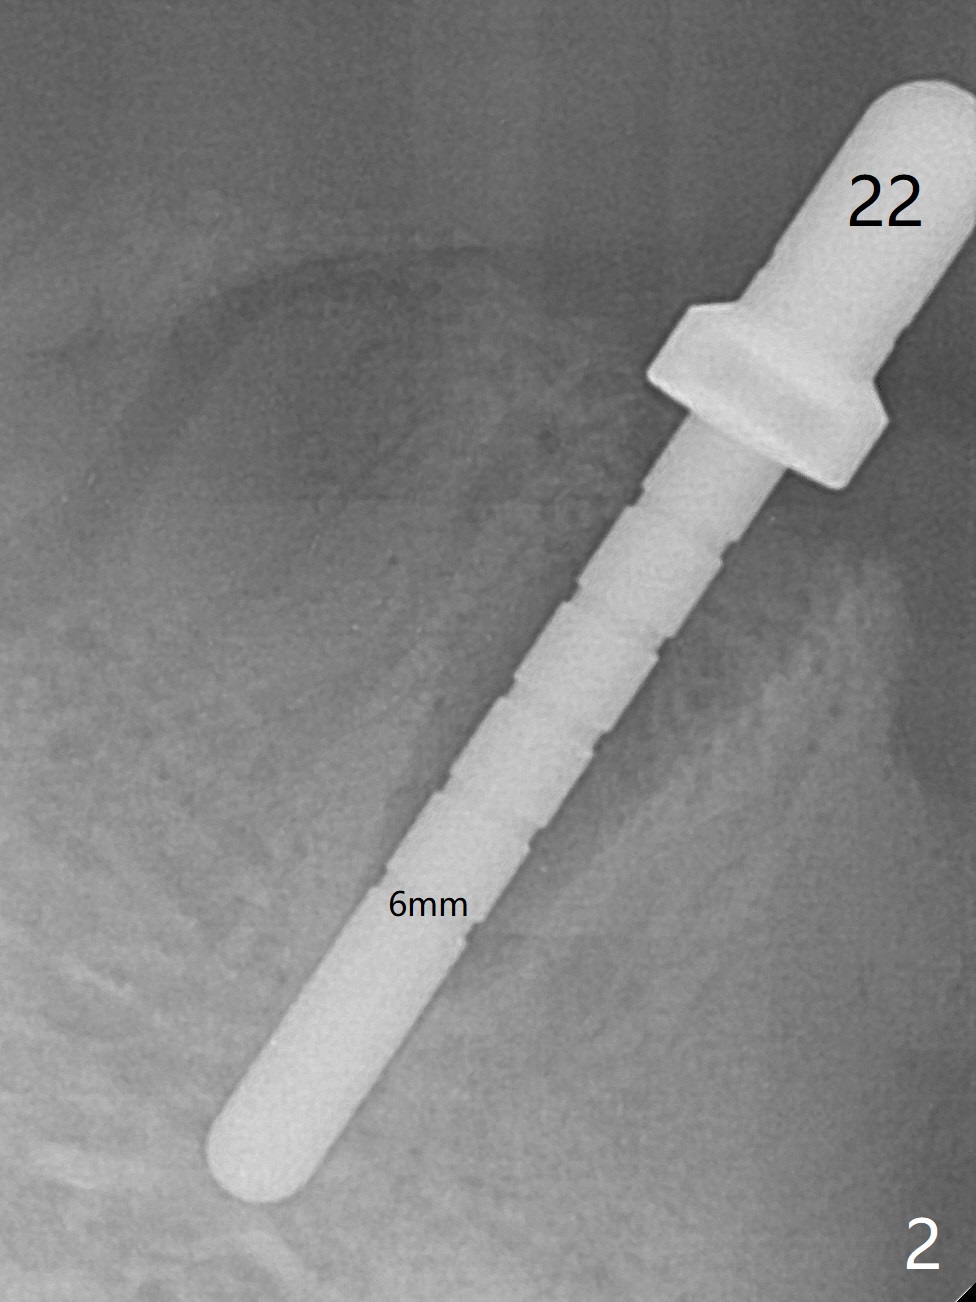

The ridge at #27 is narrow and is reduced ~ 4 mm in height (Fig.1 *) to obtain ~ 4 mm buccolingual width. A 3x14 mm 1-piece implant with ball abutment is placed (Fig.3 (*: bone graft)). In contrast, there is no problem of the buccolingual width after #22 extraction; initial osteotomy depth is 14 mm to gain ~ 5 mm of the native bone for primary stability (Fig.2). Since the lingual crest is significantly lower than the buccal one, a shorter implant (2-piece, 3.8x12 mm, Fig.4) is placed so that a ball abutment with a longer cuff is chosen (4 mm). Soft reline is applied to the site of #22 with minimal retention. But the patient is pleased with the "pain-free" procedure. It appears that gingivectomy is required for the ball abutments in 2 months (Fig.5). The implants seem osteotointegrated nearly 4 months postop (Fig.6,7). Ten months postop, the patient will return for fabrication of new full dentures to correct Class II relationship. There is mild or no bone loss 2 year 4 months postop (Fig.8,9), although the housing at #27 is dislodged. Return to Lower Canine Immediate Implant, Armaments Overdentures Xin Wei, DDS, PhD, MS 1st edition 07/24/2018, last revision 12/18/2020